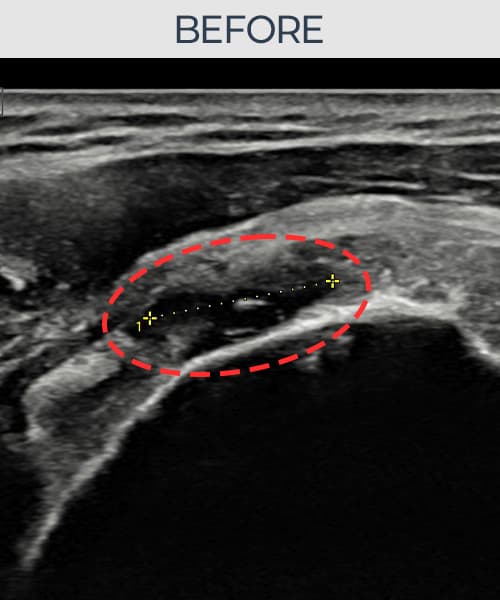

[経過期間: 23.07.31~23.09.27]

[縫縮術] 超音波検査にて左 棘上筋腱 부착부 광범위 部分断裂(13mm × 5mm (腱厚の約65%欠損))を確認。縫縮術施行後、腱の連続性が回復し、日常生活に復帰されました。